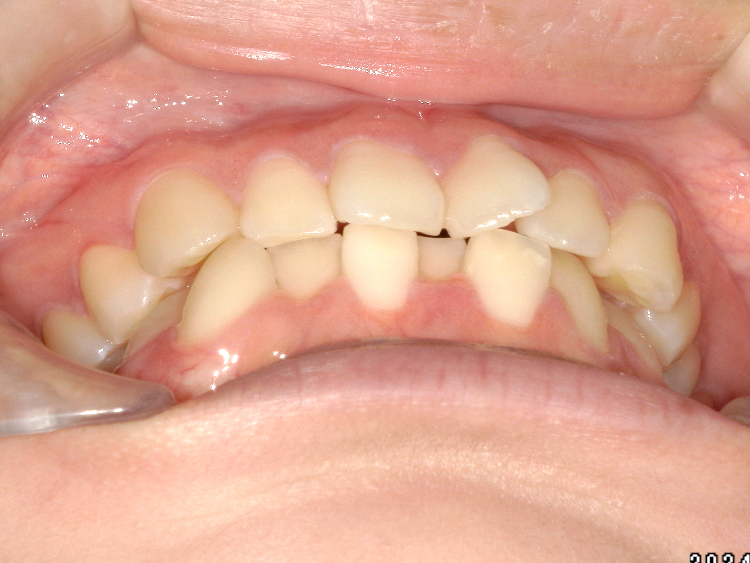

症例3

Before

After

| 主訴 | 上下の歯のガタガタを治したい |

|---|---|

| 年齢 | --- |

| 治療期間 | 約10ヶ月 |

| 治療内容 | インビザラインiGoで上下顎の治療。 狭まっていた歯並びを広げることで、 ガタガタに並んでいた歯を綺麗に並べた。 |

| 治療費 | ¥517,000(税込)+月額調整料 |

| 治療のリスク | 歯と歯の間を削ることでスペースを確保するので、 場合によっては歯が染みる症状が出ることがある。 |